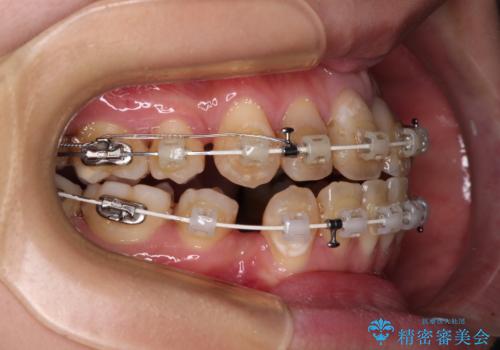

- 矯正装置

- 審美装置

- 前歯の八重歯やデコボコを気にして来院された患者様です。

口元の突出感はありませんが、前歯の重なりが著しいため、目立ちにくい表側のワイヤー装置にて、上下左右の第一小臼歯4本を抜歯して矯正治療を行うこととしました。